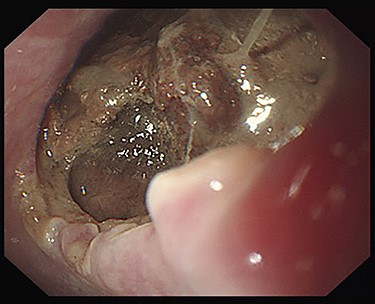

Seven days after TEVAR, the patient developed fever, and a CT scan showed bilateral iliopsoas abscesses and gas images inside the aneurysm (Fig. 2). We decided to perform upper gastrointestinal endoscopy and CT-guided drainage for abscesses. Endoscopy showed perforation of the esophageal wall and accumulation of necrotic tissue (Fig. 3).

Esophagoscopy revealing an aortoesophageal fistula covered by necrotic tissue.

The establishment of extracorporeal circulation using the femoral artery as the blood delivery route was considered difficult due to peripheral artery disease, and it was deemed impossible to use omental flap due to a history of right hemicolectomy. Therefore, in-situ reconstruction of the descending aorta seemed to be impossible, and we decided to perform bilateral axillofemoral bypass followed by descending aortic resection and esophagectomy.